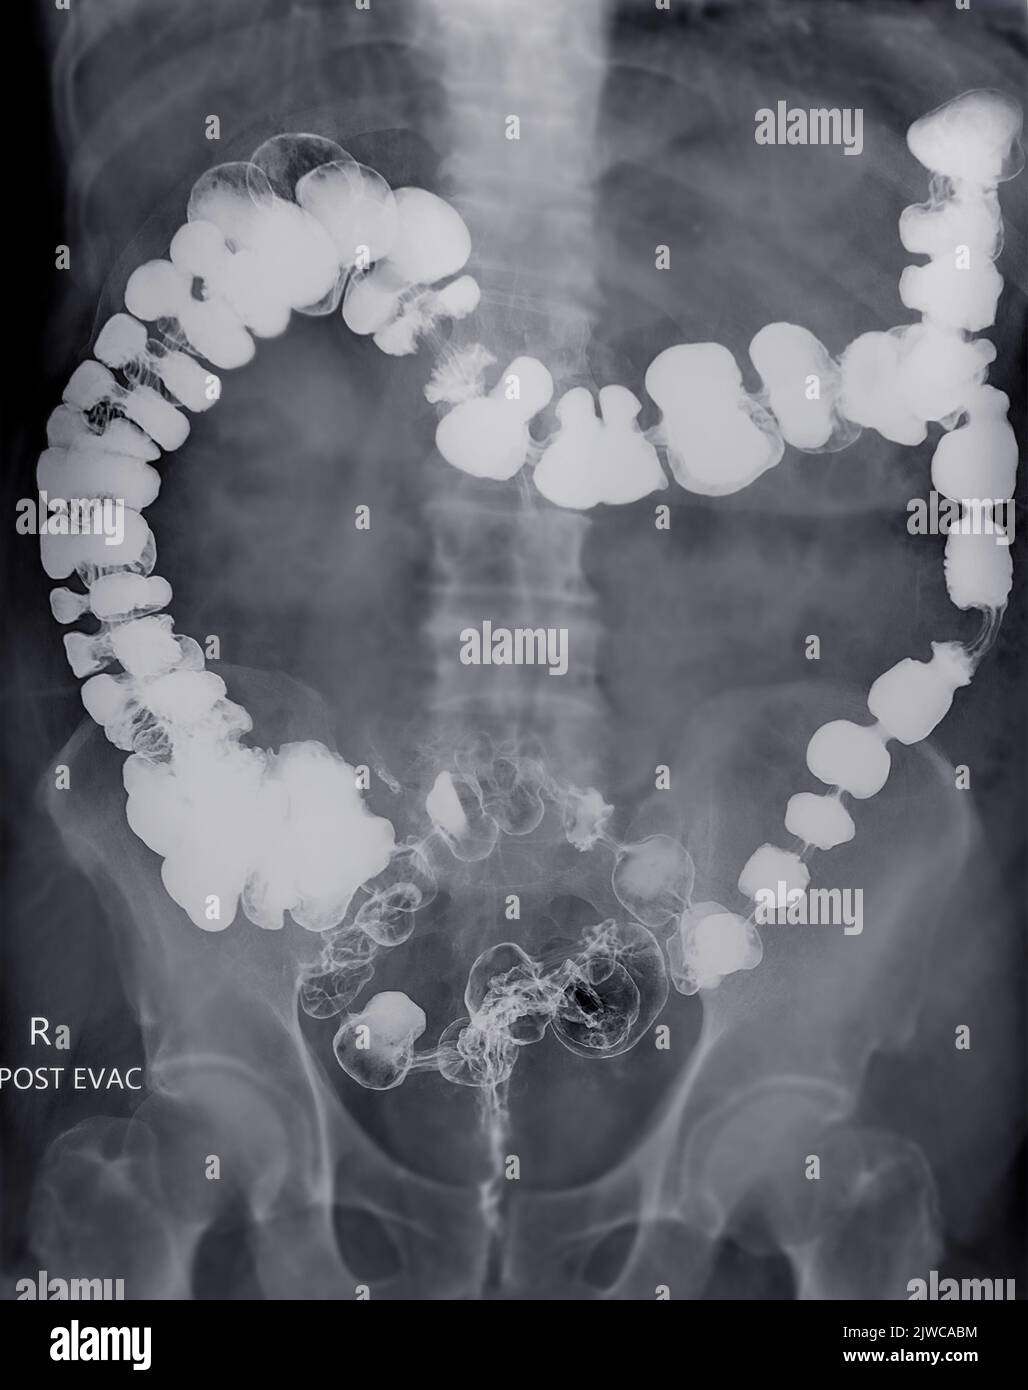

From www.alamy.com

Barium enema or BE is image of large bowel after injection of barium contrast fill into colon Chalky White Stool After Barium Enema Call your doctor if you are constipated for more than two days or if you can’t pass gas. The barium solution used during the test can cause the stool to harden, leading to difficulty passing bowel movements. It’s often mixed with water to make a thick drink that looks like a milkshake. In a barium enema, fluoroscopy allows the radiologist. Chalky White Stool After Barium Enema.

Postevacuation lateral view radiograph of a barium enema examination... Download Scientific Chalky White Stool After Barium Enema Your stools may appear white for a day or two as your body gradually clears the barium from the bowel. In a barium enema, fluoroscopy allows the radiologist to see the movement of the barium through the large intestine as it is instilled. To do a barium swallow, you swallow a chalky white substance known as barium. What are the. Chalky White Stool After Barium Enema.